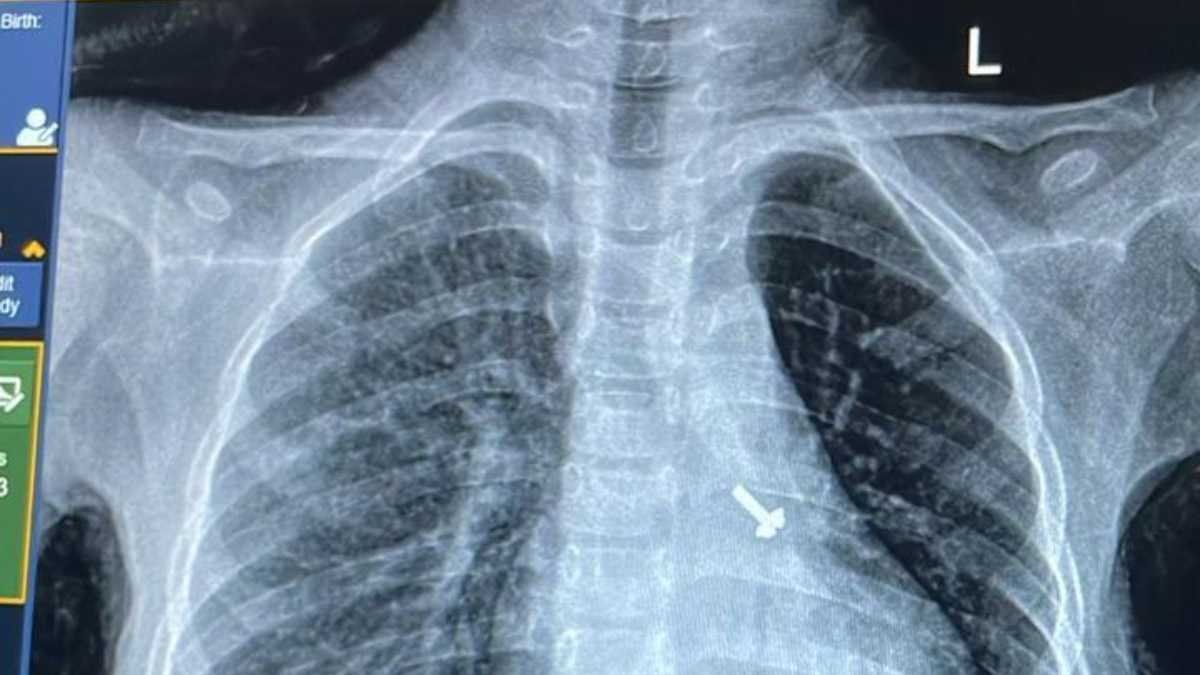

बालरोग विशेषज्ञ डॉ. व्यास कुमार राठौड़ के मुताबिक बच्चे की कुछ प्रारंभिक जांचें कराई गईं, जिसमें उसकी छाती के एक्स-रे एवं सीटी स्कैन में बच्चे के फेफड़े में एक पेंच दिखाई दिया है । इस विषय में चिकित्सक द्वारा बच्चे के अभिभावकों से पूछे जाने पर उन्हें बताया गया कि बच्चे ने घर में खेल-खेल में पेंच निगल लिया, जिसका पता परिजनों को नहीं लग पाया ।